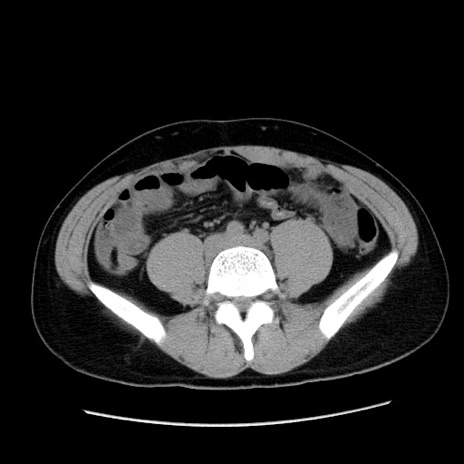

症例36(横断像)

【症例】20歳代 男性

【主訴】心窩部痛

【現病歴】今朝より上腹部痛あり。一旦軽快していたが再度出現したため救急要請。昨日夕に白身の魚を含む刺身を食べた。

【身体所見】BP 136/89mmHg、HR 74/min、BT 37.0℃、腹部:膨満、軟、心窩部に圧痛あり。反跳痛なし、筋性防御なし、腸雑音やや亢進あり。

【データ】WBC 17700、CRP 0.48